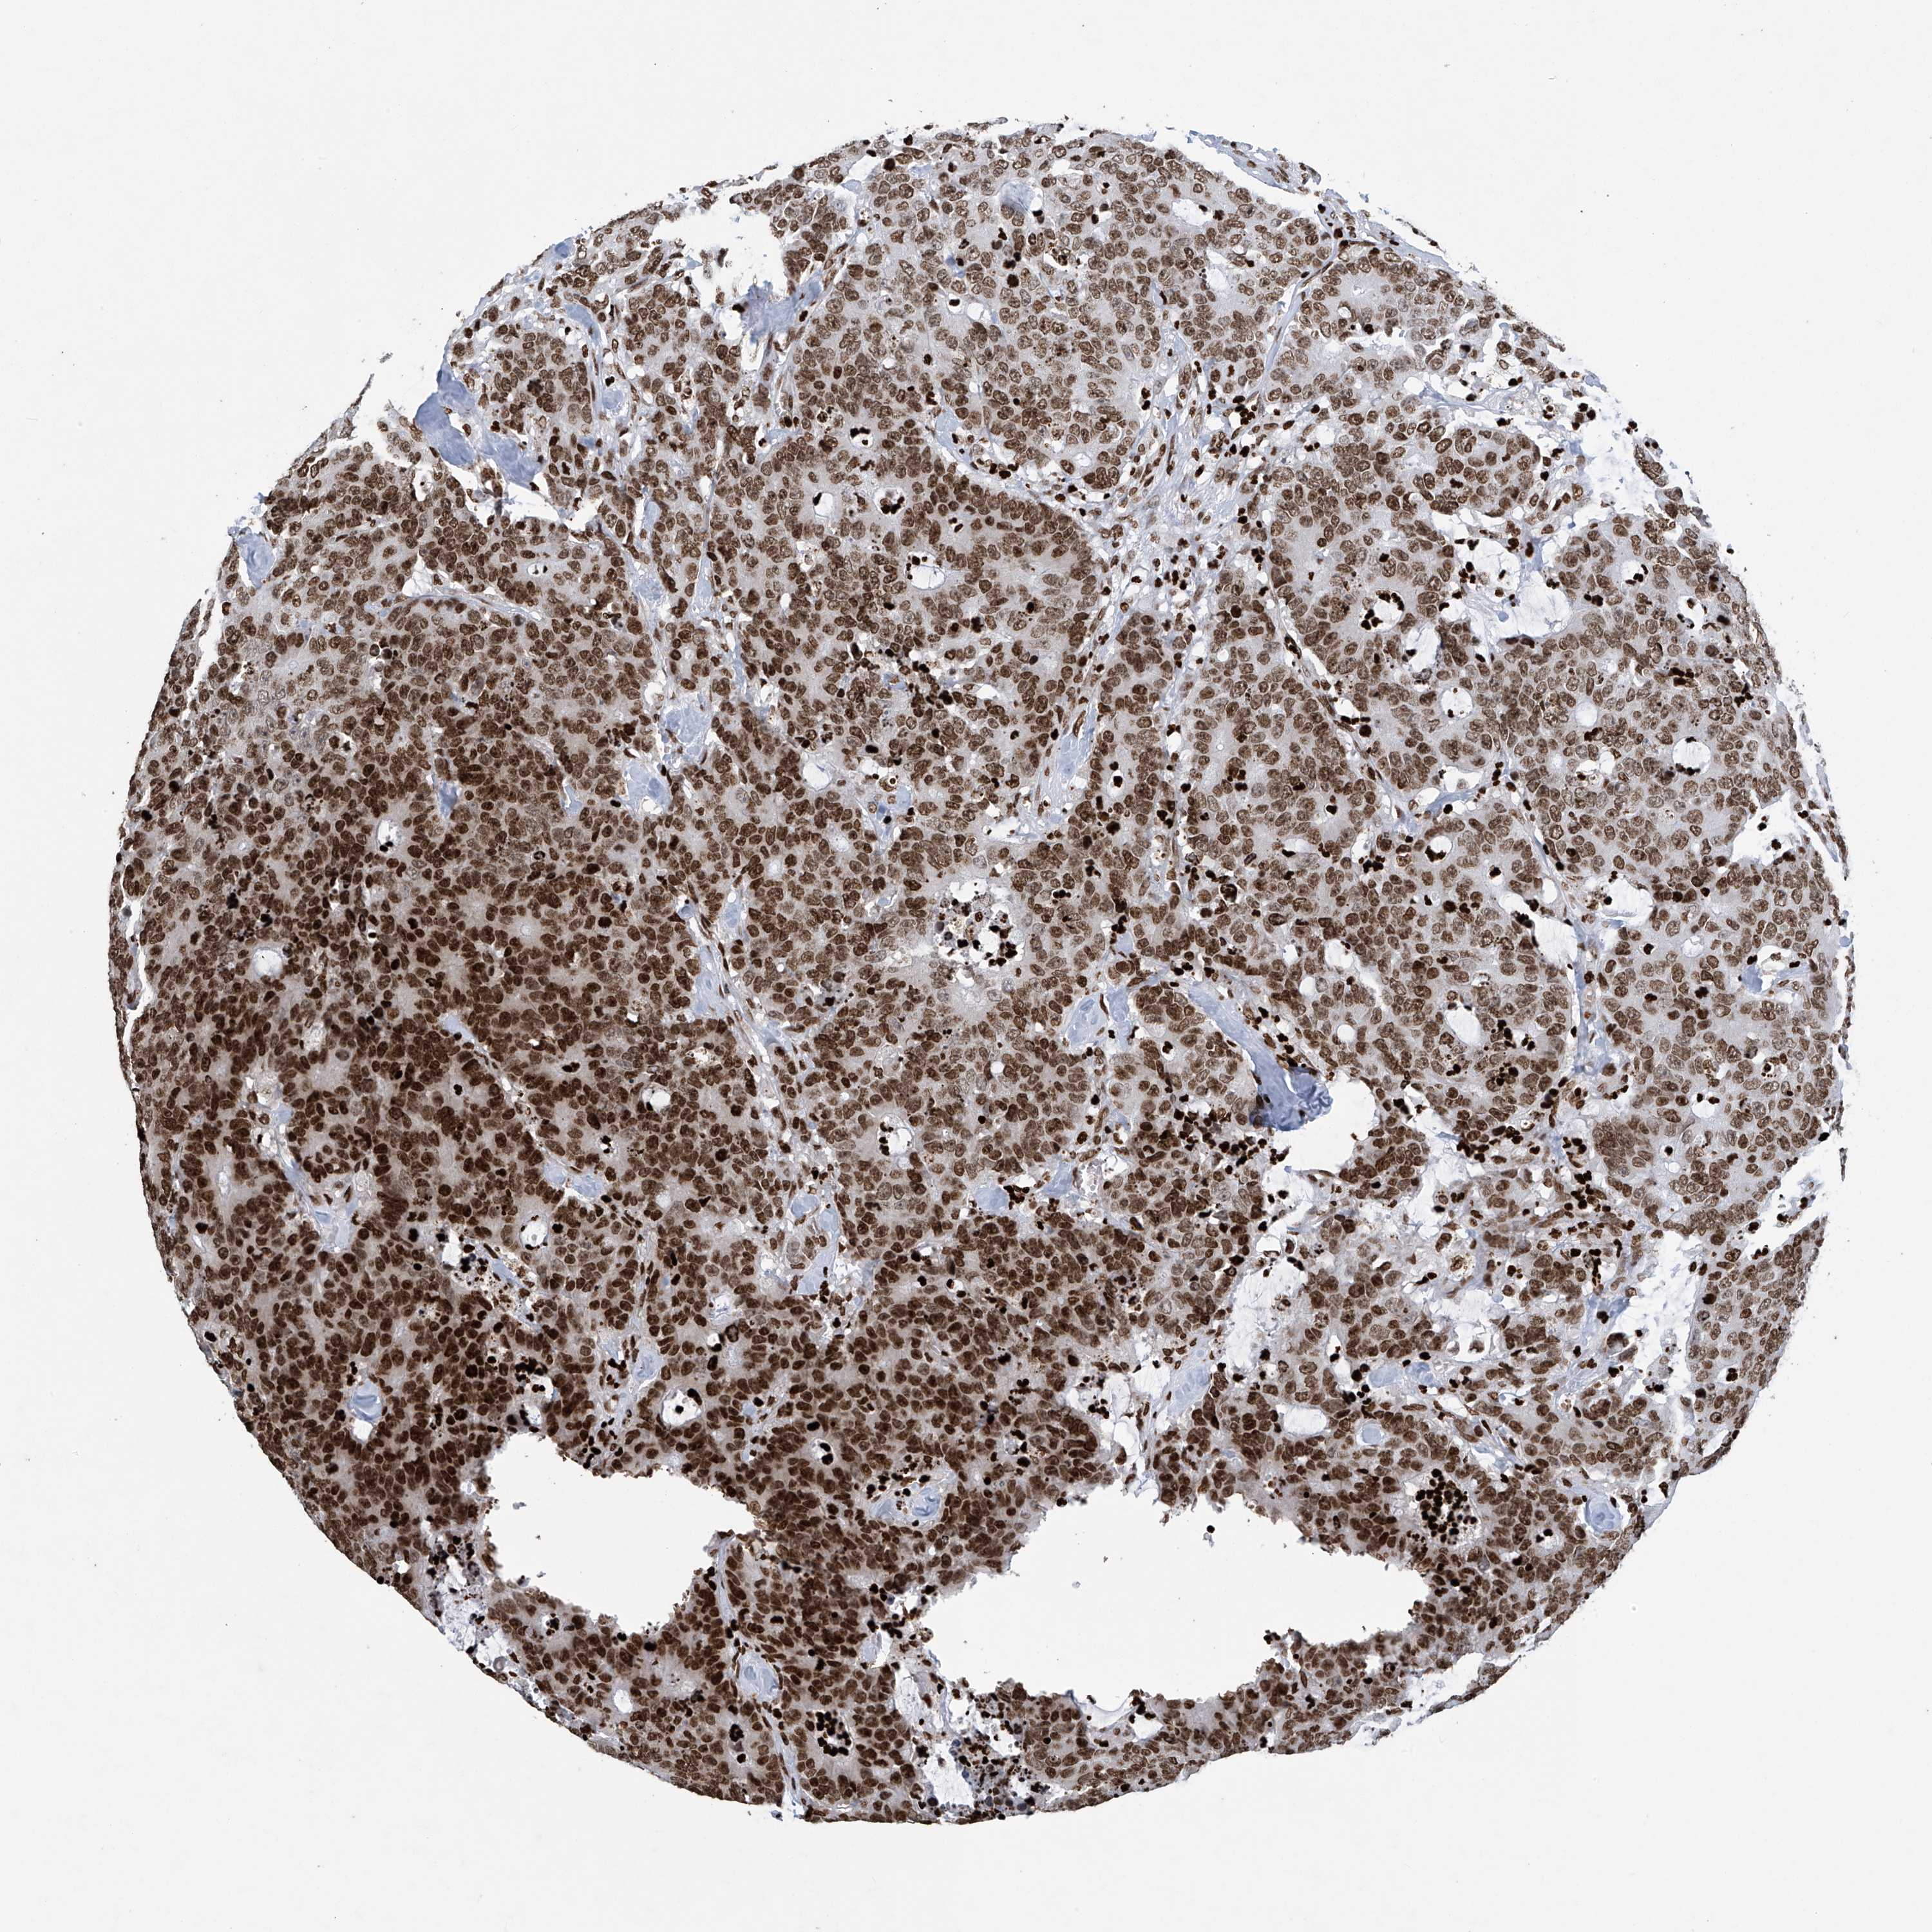

COLON ADENOCARCINOMA (VALIDATION) - Interactive survival scatter ploti

The Survival Scatter plot shows the clinical status (i.e. dead or alive) for all individuals in the patient cohort, based on the same data that underlies the corresponding Kaplan-Meier plots. Patients that are alive at last time for follow-up are shown in blue and patients who have died during the study are shown in red.

The x-axis shows the expression levels (FPKM) of the investigated gene in the tumor tissue at the time of diagnosis. The y-axis shows the follow-up time after diagnosis (years). Both axes are complimented with kernel density curves demonstrating the data density over the axes. The top density plot shows the expression levels (FPKM) distribution among dead (red) and alive patients (blue). The right density plot shows the data density of the survived years of dead patients with high and low expression levels respectively, stratified using the cutoff indicated by the vertical dashed line through the Survival Scatter plot. This cutoff is automatically defined based on the FPKM cutoff that minimizes the p-score. The cutoff can be changed by dragging the vertical line or by entering a cutoff value in the square labeled "Current cut-off".

Under the Survival Scatter plot the p-score landscape (black curve; left axis) is shown together with dead median separation (red curve; right axis). Dead median separation is the difference in median mRNA expression between patients who have died with high and low expression, respectively. It is calculated as follows: median FPKM expression of dead patients with high expression - median FPKM expression of dead patients with low expression. This is intended to aid the user in visually exploring custom cutoffs and the associated p-scores and dead median separation.

Individual patient data is displayed and can be filtered by clicking on one or more of the category buttons on the top of the page. Categories describing expression level and patient information include: high, low, alive, dead, female, male and tumor stages. The scale of the x-axis can be toggled between linear and log-scale by clicking on the "x log" button. Mouse-over function shows TCGA ID, patient information and mRNA expression (FPKM) for each patient.

& Survival analysisi

Kaplan-Meier plots summarize results from analysis of correlation between mRNA expression level and patient survival. Patients were divided based on level of expression into one of the two groups "low" (under cut off) or "high" (over cut off). X-axis shows time for survival (years) and y-axis shows the probability of survival, where 1.0 corresponds to 100 percent.

H4C16 is not prognostic in Colon Adenocarcinoma (validation)

Best expression cut offi

Based on the FPKM value of each gene, patients were classified into two groups and association between prognosis (survival) and gene expression (FPKM) was examined. The best expression cut-off refers the FPKM value that yields maximal difference with regard to survival between the two groups at the lowest log-rank P-value. Best expression cut-off was selected based on survival analysis .

When clicking on this number, the vertical dashed line indicating cut-off, the interactive survival plot, and the Kaplan-Meier curve will be adjusted to show results based on the best expression cut-off.

: 57.5

Median expressioni

Median expression refers to the median FPKM value calculated based on the gene expression (FPKM) data from all patients in this dataset. When clicking on this number, the vertical dashed line indicating cut-off, the interactive survival plot, and the Kaplan-Meier curve will be adjusted to show results based on the median expression.

: N/A

P scorei

Log-rank P value for Kaplan-Meier plot showing results from analysis of correlation between mRNA expression level and patient survival.

N/A

5-year survival highi

5-year survival for patients with higher expression than the expression cutoff.

For melanoma and glioma, 3-year survival is shown.

5-year survival lowi

5-year survival for patients with lower expression than the expression cutoff.

TCGA RNA samplesi

RNA-seq data is reported as average FPKM (number Fragments Per Kilobase of exon per Million reads), generated by the The Cancer Genome Atlas (TCGA) .

Normal distribution across the dataset is visualized with box plots, shown as median and 25th and 75th percentiles. Points are displayed as outliers if they are above or below 1.5 times the interquartile range. FPKM values of the individual samples are presented next to the box plot.

Average pTPM 67.2

Number of samples 486